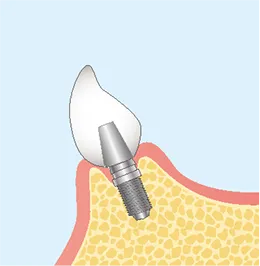

インプラント治療は、一般的に「一次手術」と「二次手術」の2段階で行われます。

流れを正しく理解することは、納得して治療を受けるために大切なステップです。

FLOW02

二次オペ

(アバットメントの装着)-

FLOW03

上部構造

(人工歯)の装着最終的な被せ物(上部構造)を製作・装着します。